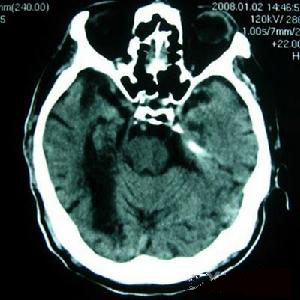

3.頭部CT、MRI顯示有典型的囊蟲改變。

其他輔助檢查:頭顱平片可發現已鈣化的囊蟲結節,陽性率為10%左右。CT的陽性率則可高達90%以上。不同病期的腦囊蟲在CT上的表現差異很大,當囊蟲寄生於腦實質時,典型的有以下4種表現:①小的鈣化灶或肉芽腫,反映了死亡的囊蟲;②圓形的低密度灶,造影后不被增強,反映了活的蟲體;③低密度或等密度的病灶,造影后有環狀強化,反映了囊蟲導致的腦部炎症;④大腦瀰漫性水腫,伴有腦室縮小及多發的造影后可增強的小結節(造影前不能發現)。當蟲體寄生於蛛網膜下腔時,CT上主要表現為腦脊液通路受阻引起的腦水腫,蛛網膜炎引起的大腦幕和腦底池異常增強以及多發性的腦梗死和腦橋池、交叉池、大腦側裂等處的低密度灶。

MRI圖像早期囊尾蚴存活時在T1加權上呈低信號區,在T2加權上呈高信號區。腦室內囊蟲在MRI圖像上囊蟲包囊呈低信號區,囊尾蚴的頭節則表現為高信號的斑點狀結節。一般來說,MRI較CT對蛛網膜下腔、腦幹、小腦及腦室內的豬囊尾蚴病診斷敏感率更高,且能分辨頭節的死活,具有檢驗療效的作用。